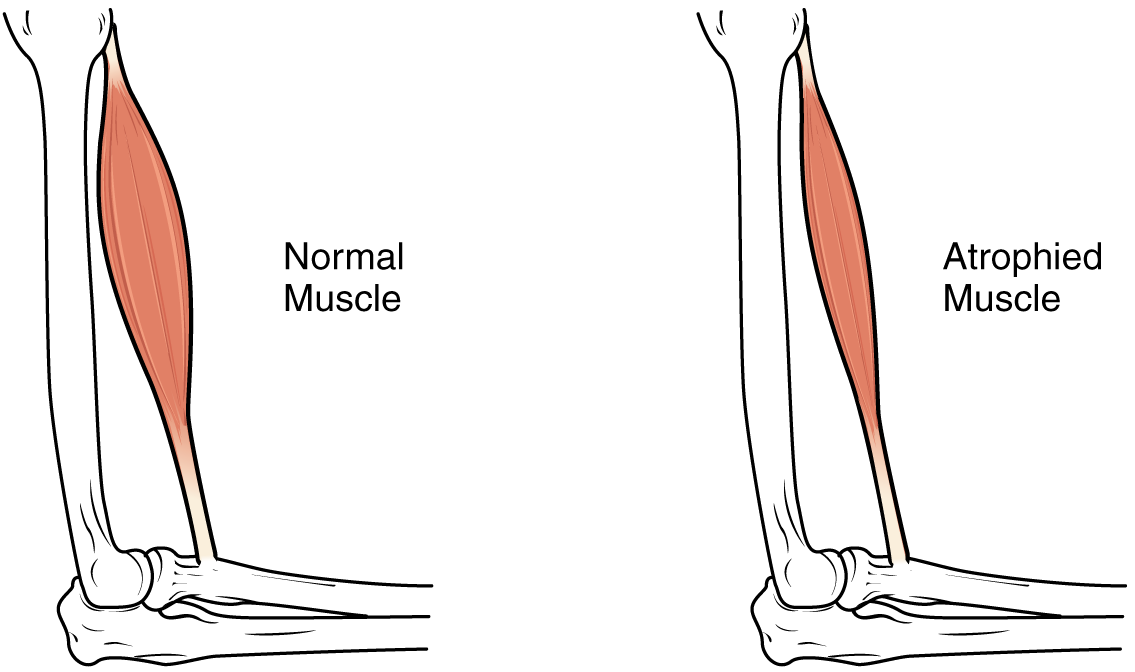

근육의 상태와 관련된 용어에는 여러 가지가 있다. 근비대와 근위축 등이 이에 해당한다.

8. 1. 근비대 (Hypertrophy)와 근위축 (Atrophy)

근비대는 개별 근육 세포의 크기 증가로 인한 근육 크기 증가이다. 이는 일반적으로 운동의 결과로 발생한다.